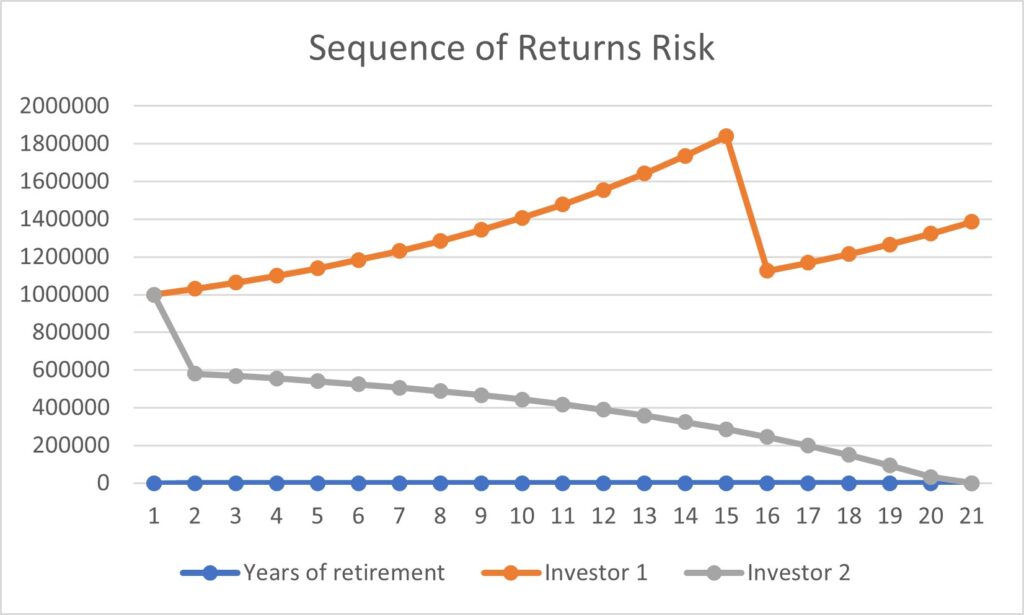

At the individual level, some of the barriers include decreased opportunities to provide accurate smoking history in the EMR, cost concerns related to insurance coverage of LCS and subsequent followups (Fig. 3), challenges to understanding LCS results when examinations show abnormal findings, fragmentation of care for management of abnormal LCS results and incidental findings, and difficulties navigating the complexities of health care systems [4, 8, 10]. Cost transparency and cost concerns are areas of active research, because cost influences how patients access and use health services [2]. For example, a recently published study evaluated the out-of-pocket cost of invasive procedures after LCS and showed that the rates of invasive procedures in commercially insured populations exceed those of invasive procedures in clinical trial participants [2].

At the community and health care system level, some of the barriers are lack of health insurance coverage for LCS under the new USPSTF guidelines and barriers to telemedicine and broadband Internet access for conducting shared decision-making telehealth encounters. Uncertainty in defining the population-level health data of patients who meet eligibility criteria and would benefit from LCS, the absence of American College of Radiology (ACR)–accredited radiology practices performing LCS in communities, and a lack of community-based strategies to increase participation among underserved communities are additional barriers at this level [4, 5, 8, 10].

At the individual level, facilitators of opportunities for LCS include increasing the opportunities to provide an accurate smoking history through educational campaigns and additional opportunities in other health encounters to capture LCS eligibility information [24]. For identifying LCS-eligible patients, leveraging teachable moment and care coordination strategies during existing routine appointments can be effective. A previous study showed that among women undergoing screening mammography who were given a brief survey to assess LCS eligibility, only a small fraction of LCS-eligible women had undergone LCS [25].

Facilitating care coordination and overcoming transportation barriers can provide additional opportunities for patients to undergo LCS [4, 26]. For example, same-day screening appointments at the time of other medical appointments have been shown to be beneficial to patients who have trouble with transportation, taking time off from work, and finding assistance with dependent care, and this strategy could be expanded to be offered to patients eligible for LCS [27]. Concerns about the costs of LCS can be alleviated by providing information about expected costs related to LCS and by offering information about diverse financial support options provided by institutions. People who are uninsured or have concerns about out-of-pocket expenses related to LCS can be referred to community health care workers and patient navigators who can assist patients in identifying grant funding and institutional financial assistance programs to cover LCS among patients who do not have insurance or have a low income [22, 28]. Health care workers can also assist patients in navigating the complexities of the health care system and clarify additional questions related to their LCS results [22].

At the community and health care system level, facilitators of opportunities include the development of system-level policies that combine the updated USPSTF guidelines for LCS and consider social risk factors affecting patients and their communities to promote equitable LCS use and advocacy efforts that increase telehealth and patient portal access by increasing broadband Internet access points and digital patient navigators among underserved communities [5, 7, 10, 12, 17]. Including social risk factors in the calculation used for new LC risk models and LCS eligibility criteria can potentially benefit racial and ethnic minority groups and other underserved patient populations [4]. Increasing access to information about local accredited LCS centers and optimizing EMR systems to identify population-level health data of eligible patients under the new guidelines are additional facilitators to aid in removing these barriers [10, 15, 22].